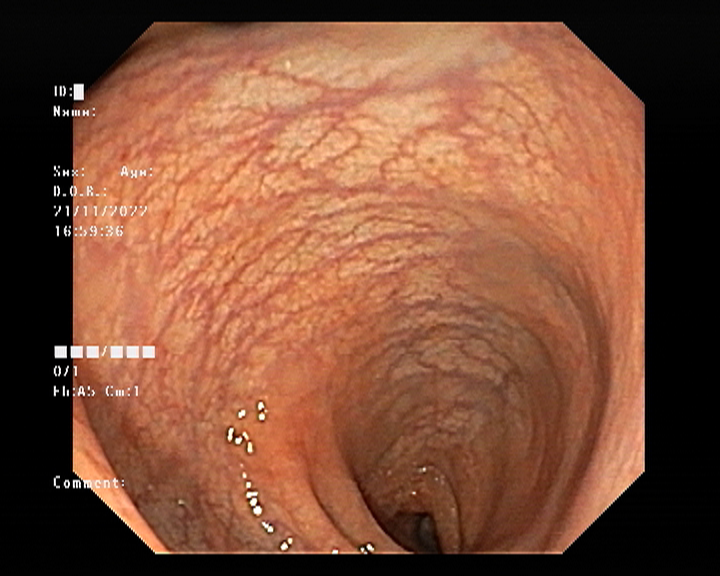

Endoscopy and colonoscopy are safe and accurate procedures used to directly examine the digestive tract and detect the root cause of chronic acidity, GERD, abdominal pain, bleeding, and bowel irregularities. These minimally invasive tests help identify ulcers, inflammation, infections, polyps, strictures, and early cancerous changes.

At Sapphire Gastroenterology Center, modern endoscopic equipment ensures precise diagnosis and, when required, therapeutic intervention during the same procedure. Based on findings, targeted treatment plans are created, including medication, diet guidance, and preventive strategies. Early diagnosis through endoscopy and colonoscopy plays a crucial role in preventing serious complications and improving long-term digestive health.